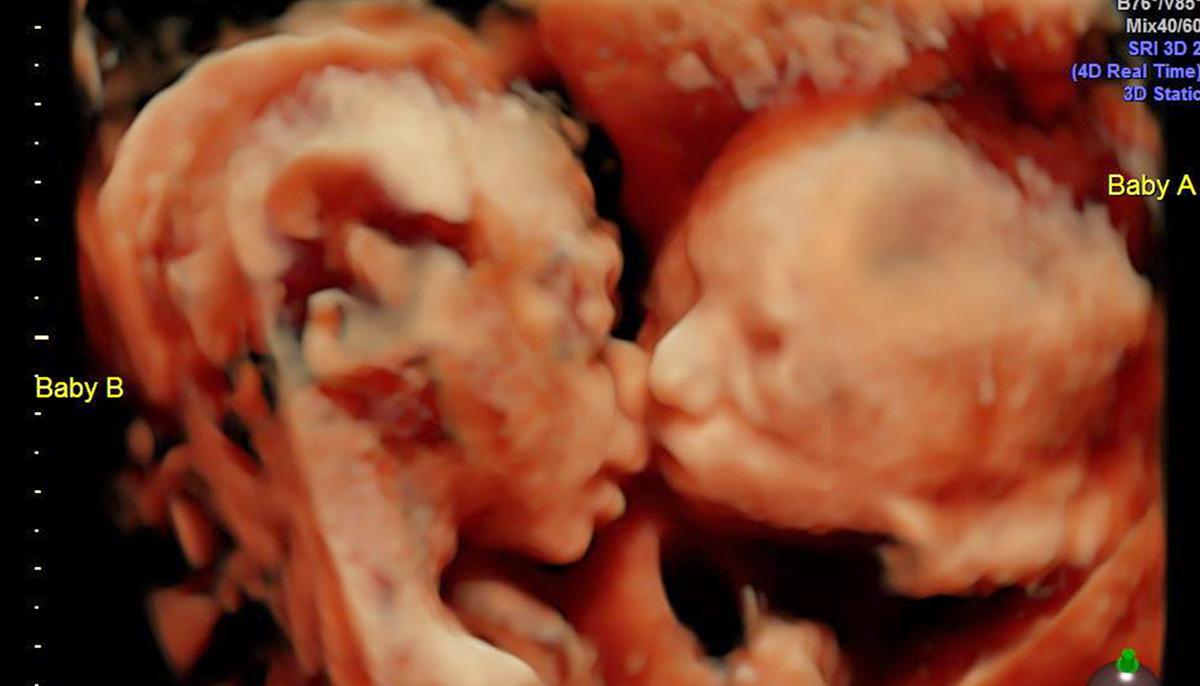

An expectant mother’s 24-week sonogram revealed her twin baby girls showing their affection for each other in the womb, and the mom-to-be and her partner decided that the image was simply too cute not to share.

First-time mom Carissa Gill and her partner, Randy Good, of Croydon, Pennsylvania, had their 4-D week-24 ultrasound at Fetal Vision Imaging in nearby Levittown. The couple later described witnessing their unborn babies sharing a sweet sisterly lip-lock as “beautiful to see.”